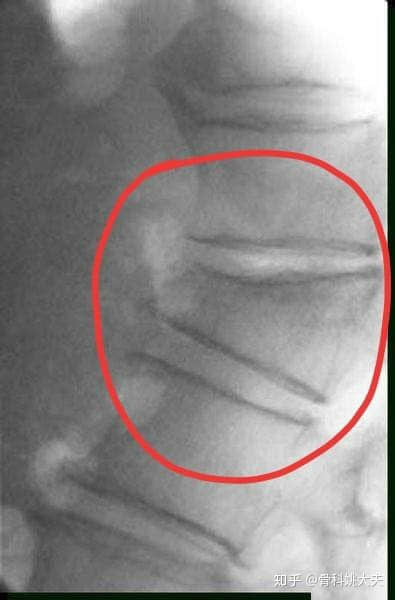

压缩性骨折就好比一个馒头被压扁了,但是又没有整个四分五裂,还是大致原来的环形轮廓。如果四分五裂了,那就是压缩性粉碎性骨折。

压缩性骨折最常出现于老年人,因为老年人的骨质疏松而导致骨质的强度明显减小,当受到垂直方向的暴力,会导致骨质的压缩变扁,从而出现压缩性骨折。

出现此类的情况多见于严重骨质疏松的老人在弯腰或者抬重东西的时候出现腰椎和胸椎的压缩性骨折。会即刻出现胸闷腰痛直不起腰,或者隐隐作痛,如果压缩性骨折并不是很严重的话,也很容易被遗漏。尤其是农村的留守老人,子女在外地工作的,来医院并不方便,所以多选择在家里面忍一忍。可随着时间的延长,疼痛并没有好转,再来医院检查的时候,骨折已经变成陈旧性的了。

有极少部分的骨折,并不会有明显的疼痛,或者只痛几天就好转了。但并不代表骨折恢复了。椎体的骨折一般要求:压缩小于1/2的可以保守治疗,卧床休息2到3个月,在医生的指导下逐渐的恢复坐立和行走。大于1/2的压缩性骨折是需要做手术的,目前常采用的治疗方案是pvp、pkp,是一种非常经济实用,效果好的治疗方案,比过去做钢板螺钉,撑开植骨要简单的多,但是任何手术方式都有它的缺点,具体情况也要具体分析。